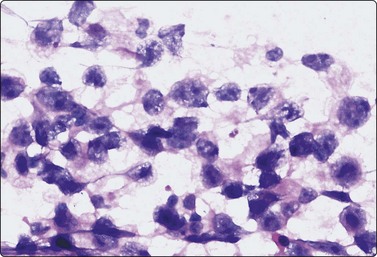

Embryonal carcinoma (Figs 13.33 and 13.34)14,58-61,63,65,66

image image

Fig. 13.33 Embryonal carcinoma

(A) Adenocarcinoma-like tissue fragment of large malignant cells with large vesicular nuclei, coarse chromatin, prominent nucleoli; prominent cytoplasmic vacuolation (MGG, HP); (B) Fragment of undifferentiated mesenchymal tissue right; cluster of malignant epithelial cells with large vesicular nuclei and prominent large nucleoli (H&E, HP) left.

image

Fig.13.34 Embryonal carcinoma

Tissue section corresponding to Fig. 13.33B (H&E, IP).

Criteria for diagnosis

Cell-rich smears,

Frequent three-dimensional clusters,

Occasional tendency to acinar and microglandular grouping,

Large vesicular, obviously malignant nuclei, large nucleoli,

Indistinct cell borders,

Basophilic to amphophilic, sometimes pale, vacuolated cytoplasm,

Immunocytochemistry: cells positive for PLAP, OCT 3/4, CD30, AE1/AE3 and CK7.

The vesicular nuclei of embryonal carcinoma are larger and more pleomorphic than those of seminoma, the chromatin is coarse and irregular and nucleoli are large, occasionally huge, and eosinophilic. The cytoplasm is pale and distinctly vacuolated, but not ‘bubbly’. It is not highly fragile and a TB as in seminoma is not seen. Cytoplasmic boundaries are poorly defined (Fig. 13.33). Hemorrhage and tumor necrosis may be prominent and may hamper the identification of diagnostic cells. It is usually not seen in smears of seminoma. Chromatin threads and reticulated material resembling TB can occur. Large syncytiotrophoblastic cells may be found. Prominent lymphoid/plasma cell infiltrates or mucus are not seen. The presence of cellular mesenchyme on its own does not warrant a designation of teratoma (Figs. 13.33B and 13.34).49